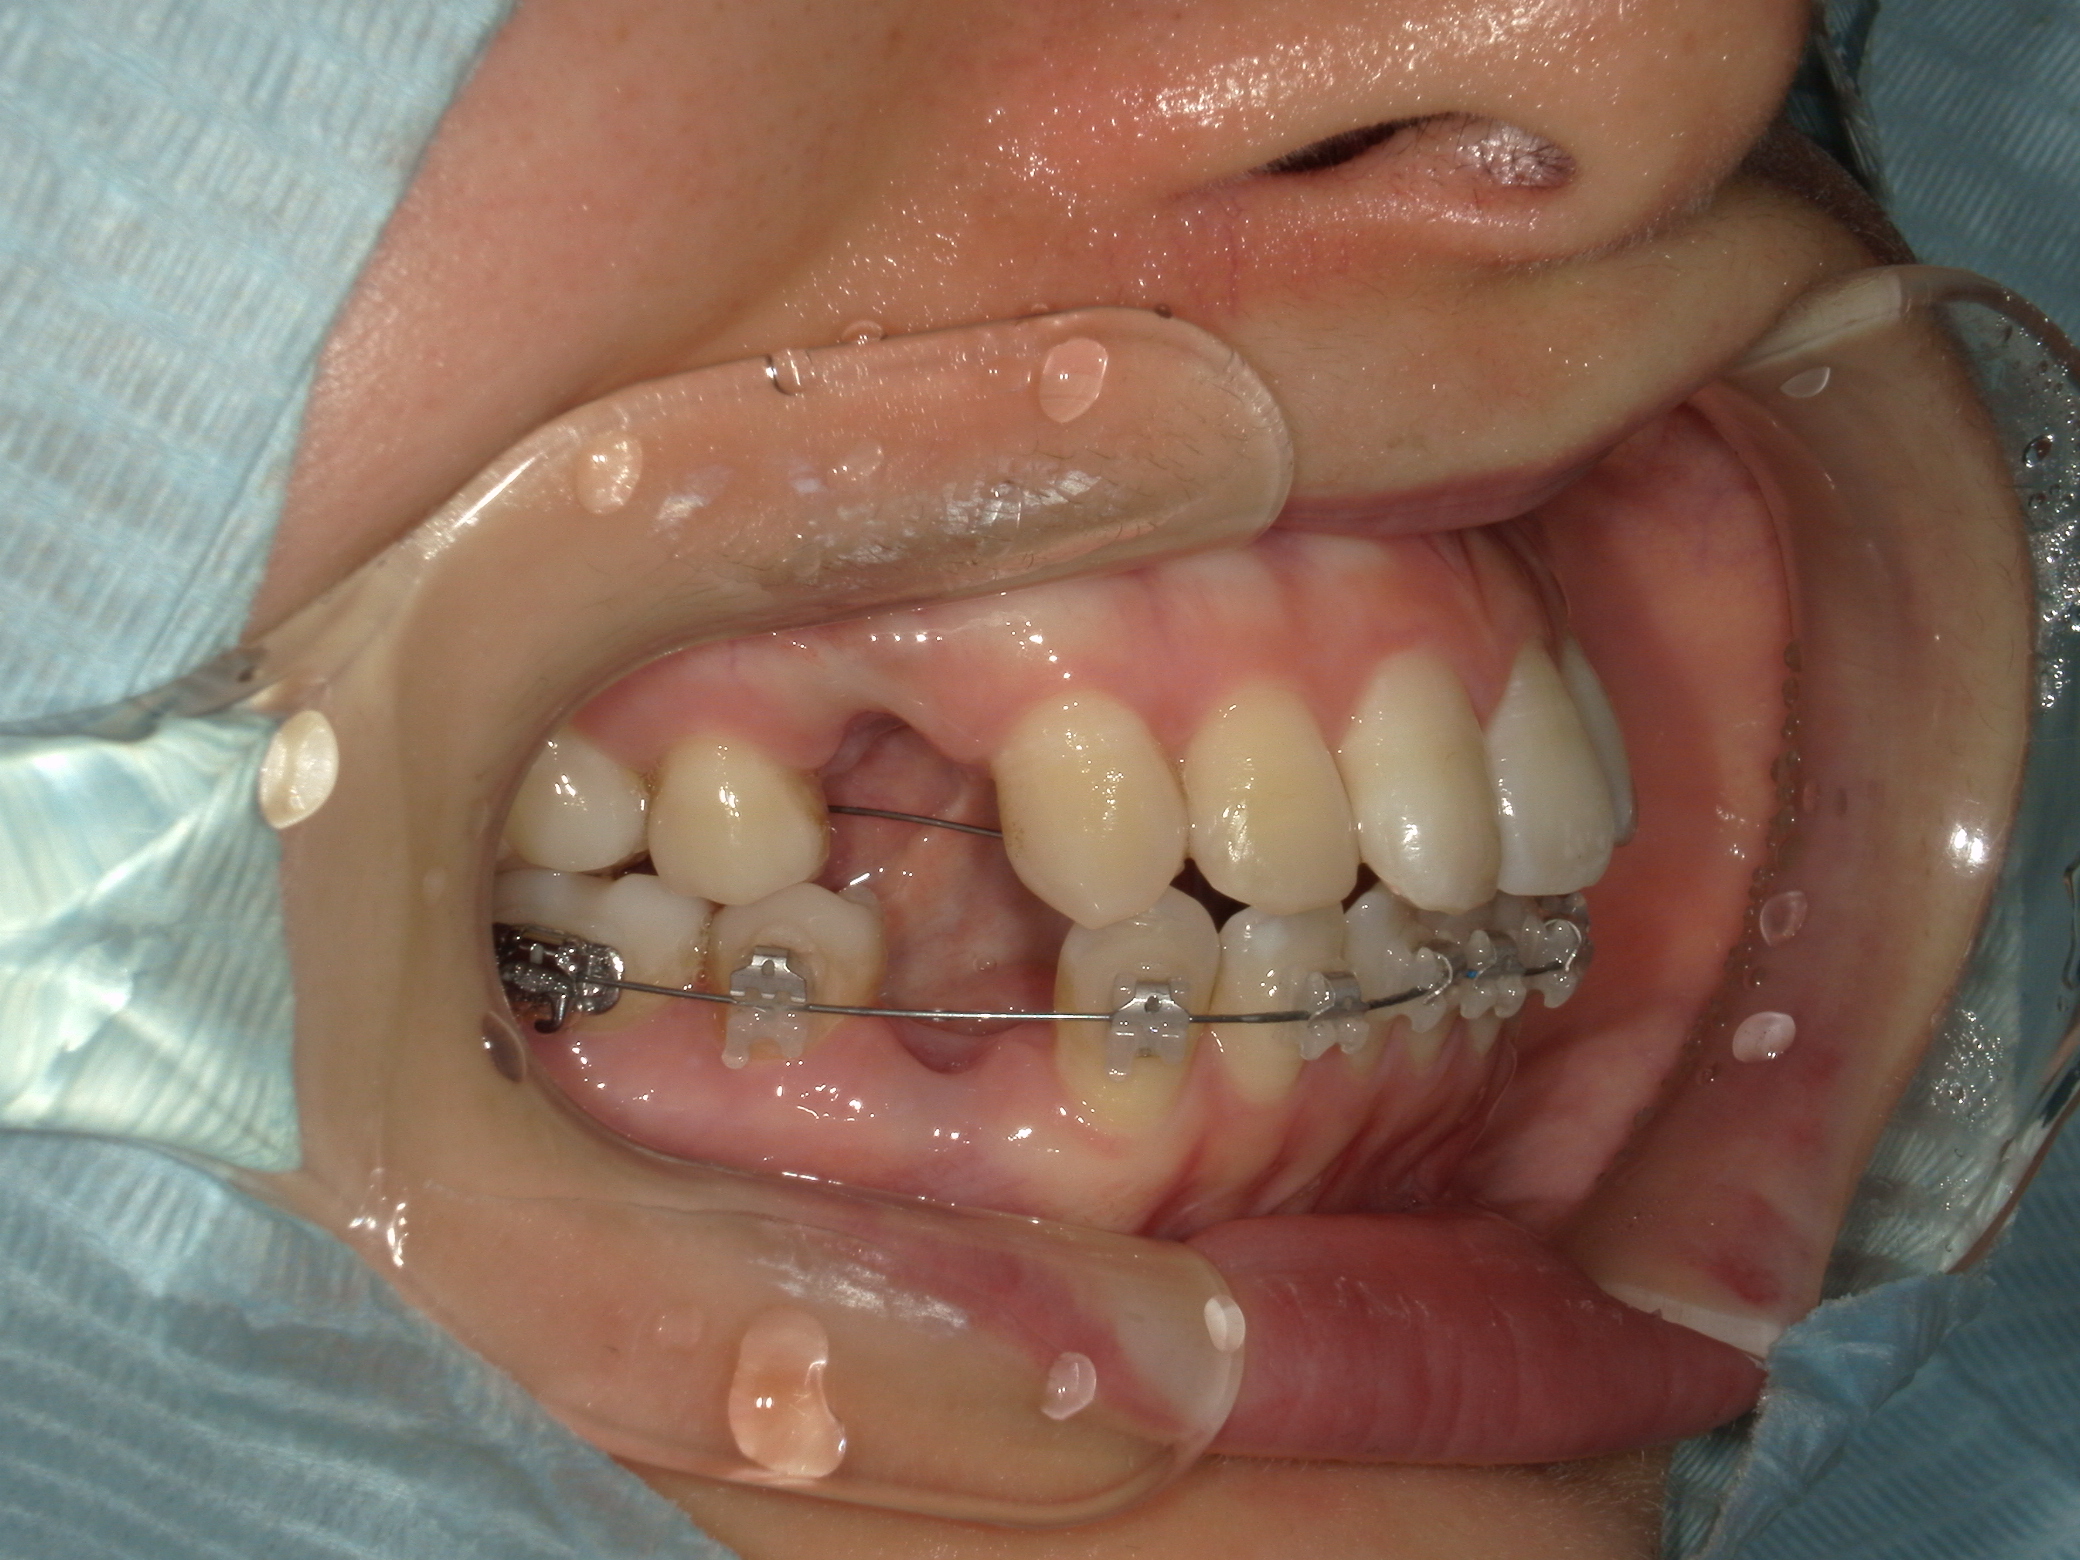

口元の突出を主訴に来院。

上下小臼歯抜歯により突出感を改善する計画を立てた。確立した咬合を崩さないように治療を進める事を目標とした。

患者はハーフリンガル矯正を希望した。